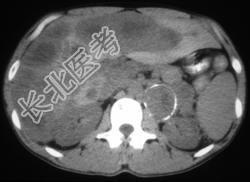

- 多项选择题男,37岁, 阵发性高血压1月余,请结合所提供图像, 选择最佳答案 ( )

A、左侧肾上腺癌

B、左侧恶性嗜铬细胞瘤

C、左侧肾上腺转移瘤

D、肝转移瘤

E、原发性肝癌